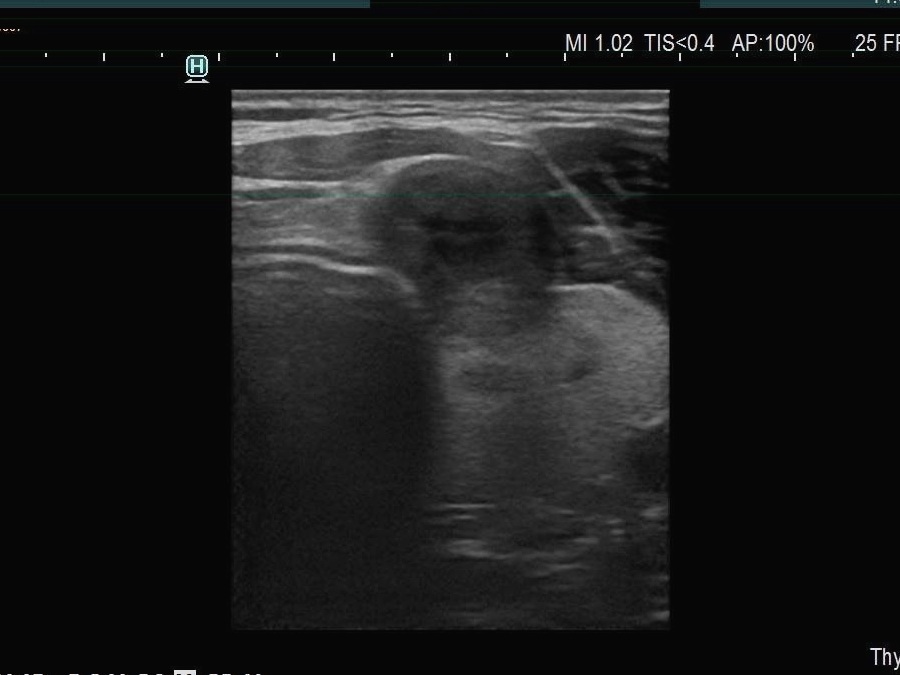

The echogenicity of the nodule - case 1740 (ultrasonographic picture 5)

Left side of the isthmus, transverse view - with decreased frequency. By using adequate settings, it turned aout that this is a solid, moderately or very hypoechoic nodule. The nodule has abutting and bulging contours.